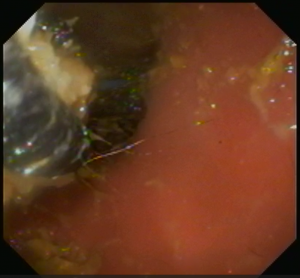

その後、胃の中まで内視鏡を進め胃内を確認したところ、幽門部にひも状の異物の塊がはまっているのを発見しました。

同じようにW字鉗子にて把持し引っ張ってこようとしましたが強固にはまっており摘出するのに少し時間を要しました。